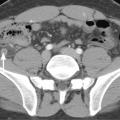

Si le médecin prescrit, c’est le radiologue qui interprète. Cela nécessite une connaissance de l’anatomie radiologique des différents organes (fig. 1 ).

Si le médecin prescrit, c’est le radiologue qui interprète. Cela nécessite une connaissance de l’anatomie radiologique des différents organes (